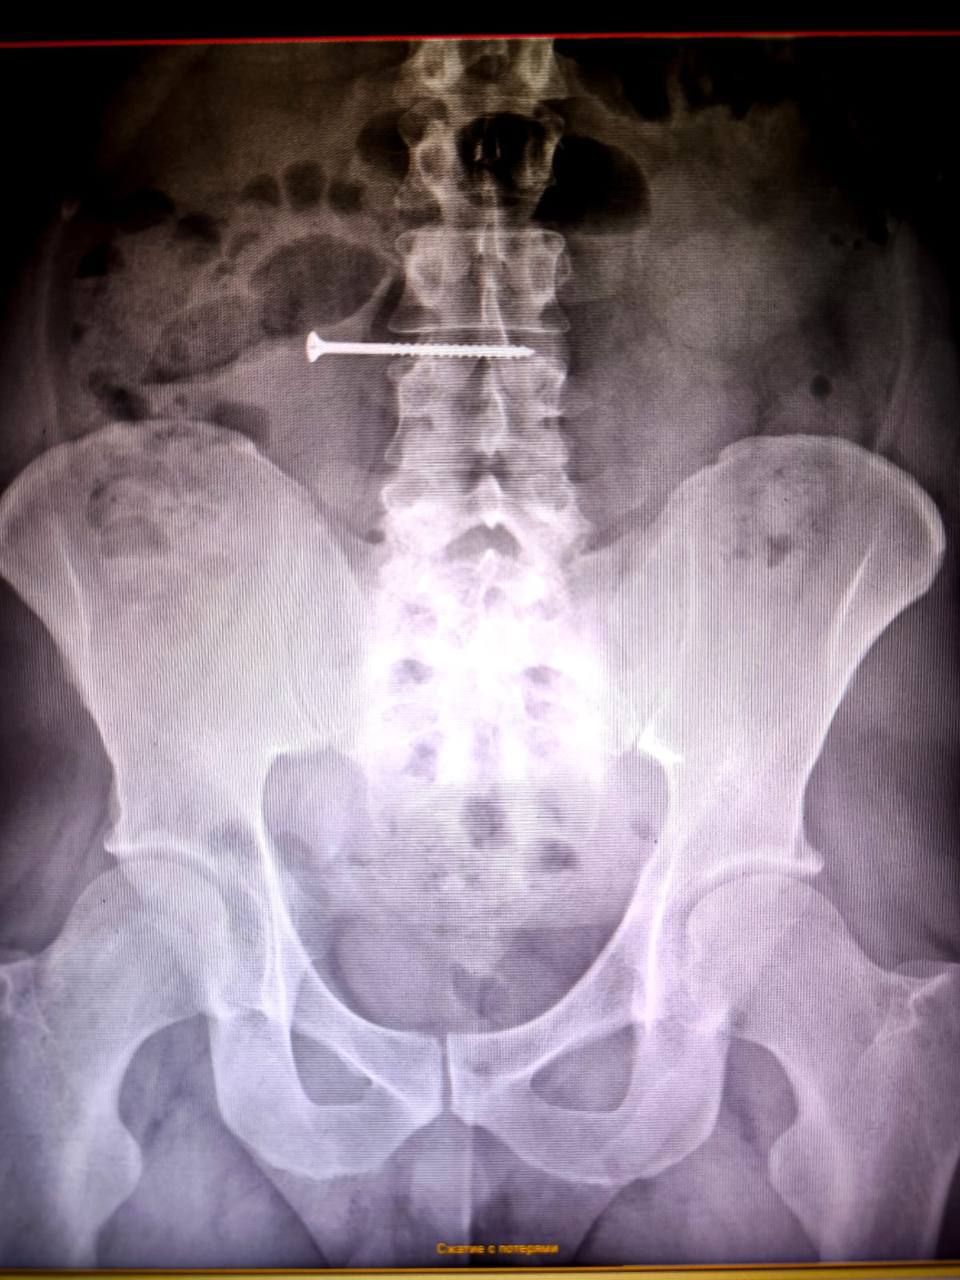

В Красноярскую краевую больницу обратился мужчина, случайно проглотивший саморез во время работы с сайдингом дома. Держа крепеж во рту, он оступился и проглотил 50-миллиметровый саморез.

Первичное обследование показало, что инородное тело находится в тонком кишечнике, что создавало высокий риск перфорации и перитонита.

Врачи экстренно провели операцию, где хирурги совместно с эндоскопистами успешно извлекли саморез. К счастью, контрольное обследование не выявило повреждений стенок желудка и кишечника.